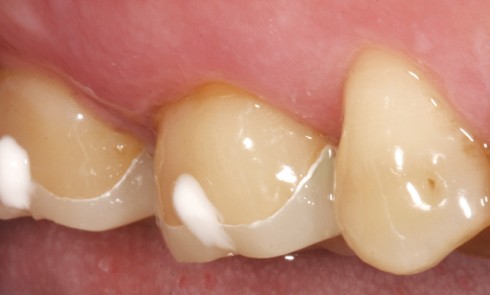

Odontologie restauratrice

Article réservé à nos abonnés Inlays et onlays en céramique : critères de succès

Avant le développement des systèmes adhésifs il y a une trentaine d’années, les restaurations indirectes au niveau des secteurs latéraux...